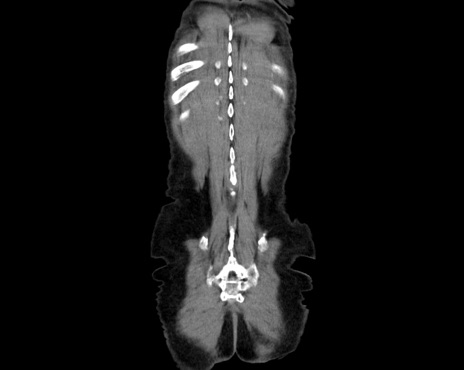

横断像

【症例】80歳代男性

【主訴】嘔吐

【現病歴】昨晩2回嘔吐あり、今朝になっても嘔吐あり。来院。

【既往歴】胃潰瘍

【身体所見】意識清明、BT 37.6℃、BP 166/95mmHg、HR 100bpm、SpO2 97%、腹部:平坦・軟、腸蠕動音聴取良好、圧痛なし。

【データ】WBC 21900、CRP 1.4